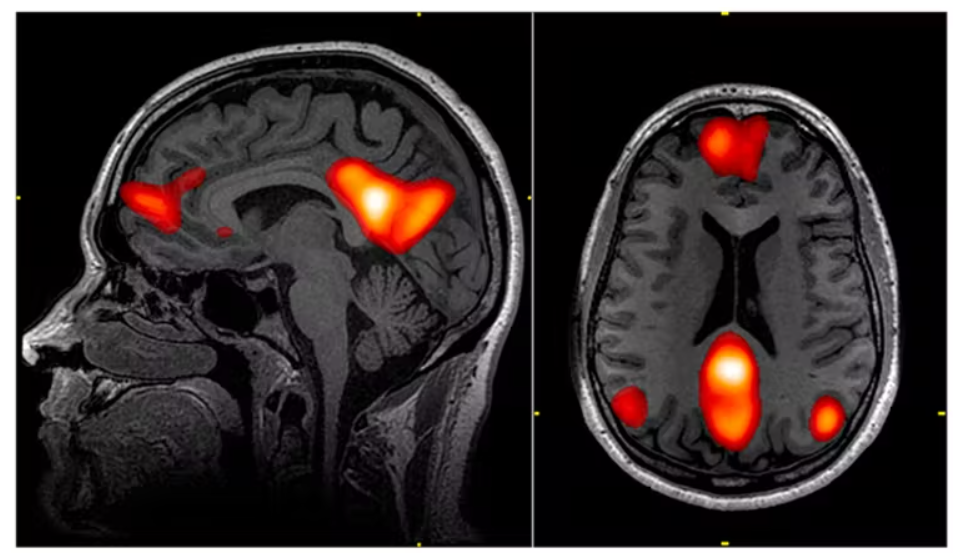

Estudios realizados con escáneres cerebrales de resonancia magnética funcional han demostrado que la psilocibina parece reducir la actividad en el córtex pre frontal medial, una zona del cerebro que ayuda a regular una serie de funciones cognitivas, como la atención, el autocontrol, los hábitos y la memoria. El compuesto también disminuye las conexiones entre esta zona y el córtex cingulado posterior.

Una conexión activa entre estas dos áreas cerebrales es normalmente una característica de la “red por defecto” del cerebro. Esta red se activa cuando descansamos y nos concentramos internamente, quizás recordando el pasado, imaginando el futuro o pensando en nosotros mismos o en los demás. Al reducir la actividad de la red, la psilocibina puede eliminar las restricciones del “yo” interno, y los usuarios informan de una “mente abierta” con una mayor percepción del mundo que les rodea.

Curiosamente, la rumiación, un estado de estar “atascado” en pensamientos negativos, particularmente sobre uno mismo, es un sello distintivo de la depresión. Y sabemos que los pacientes con mayores niveles de rumiación negativa tienden a mostrar una mayor actividad de la red por defecto en comparación con otras redes en reposo, es decir, se vuelven literalmente menos receptivos al mundo que les rodea.

Sólo un día después de la primera dosis de psilocibina, las mediciones revelaron un aumento general de la conectividad entre las distintas redes del cerebro, que suelen reducirse en las personas con depresión grave. La red por defecto se redujo simultáneamente, mientras que la conectividad entre ésta y otras redes aumentó, lo que respalda estudios anteriores más pequeños.